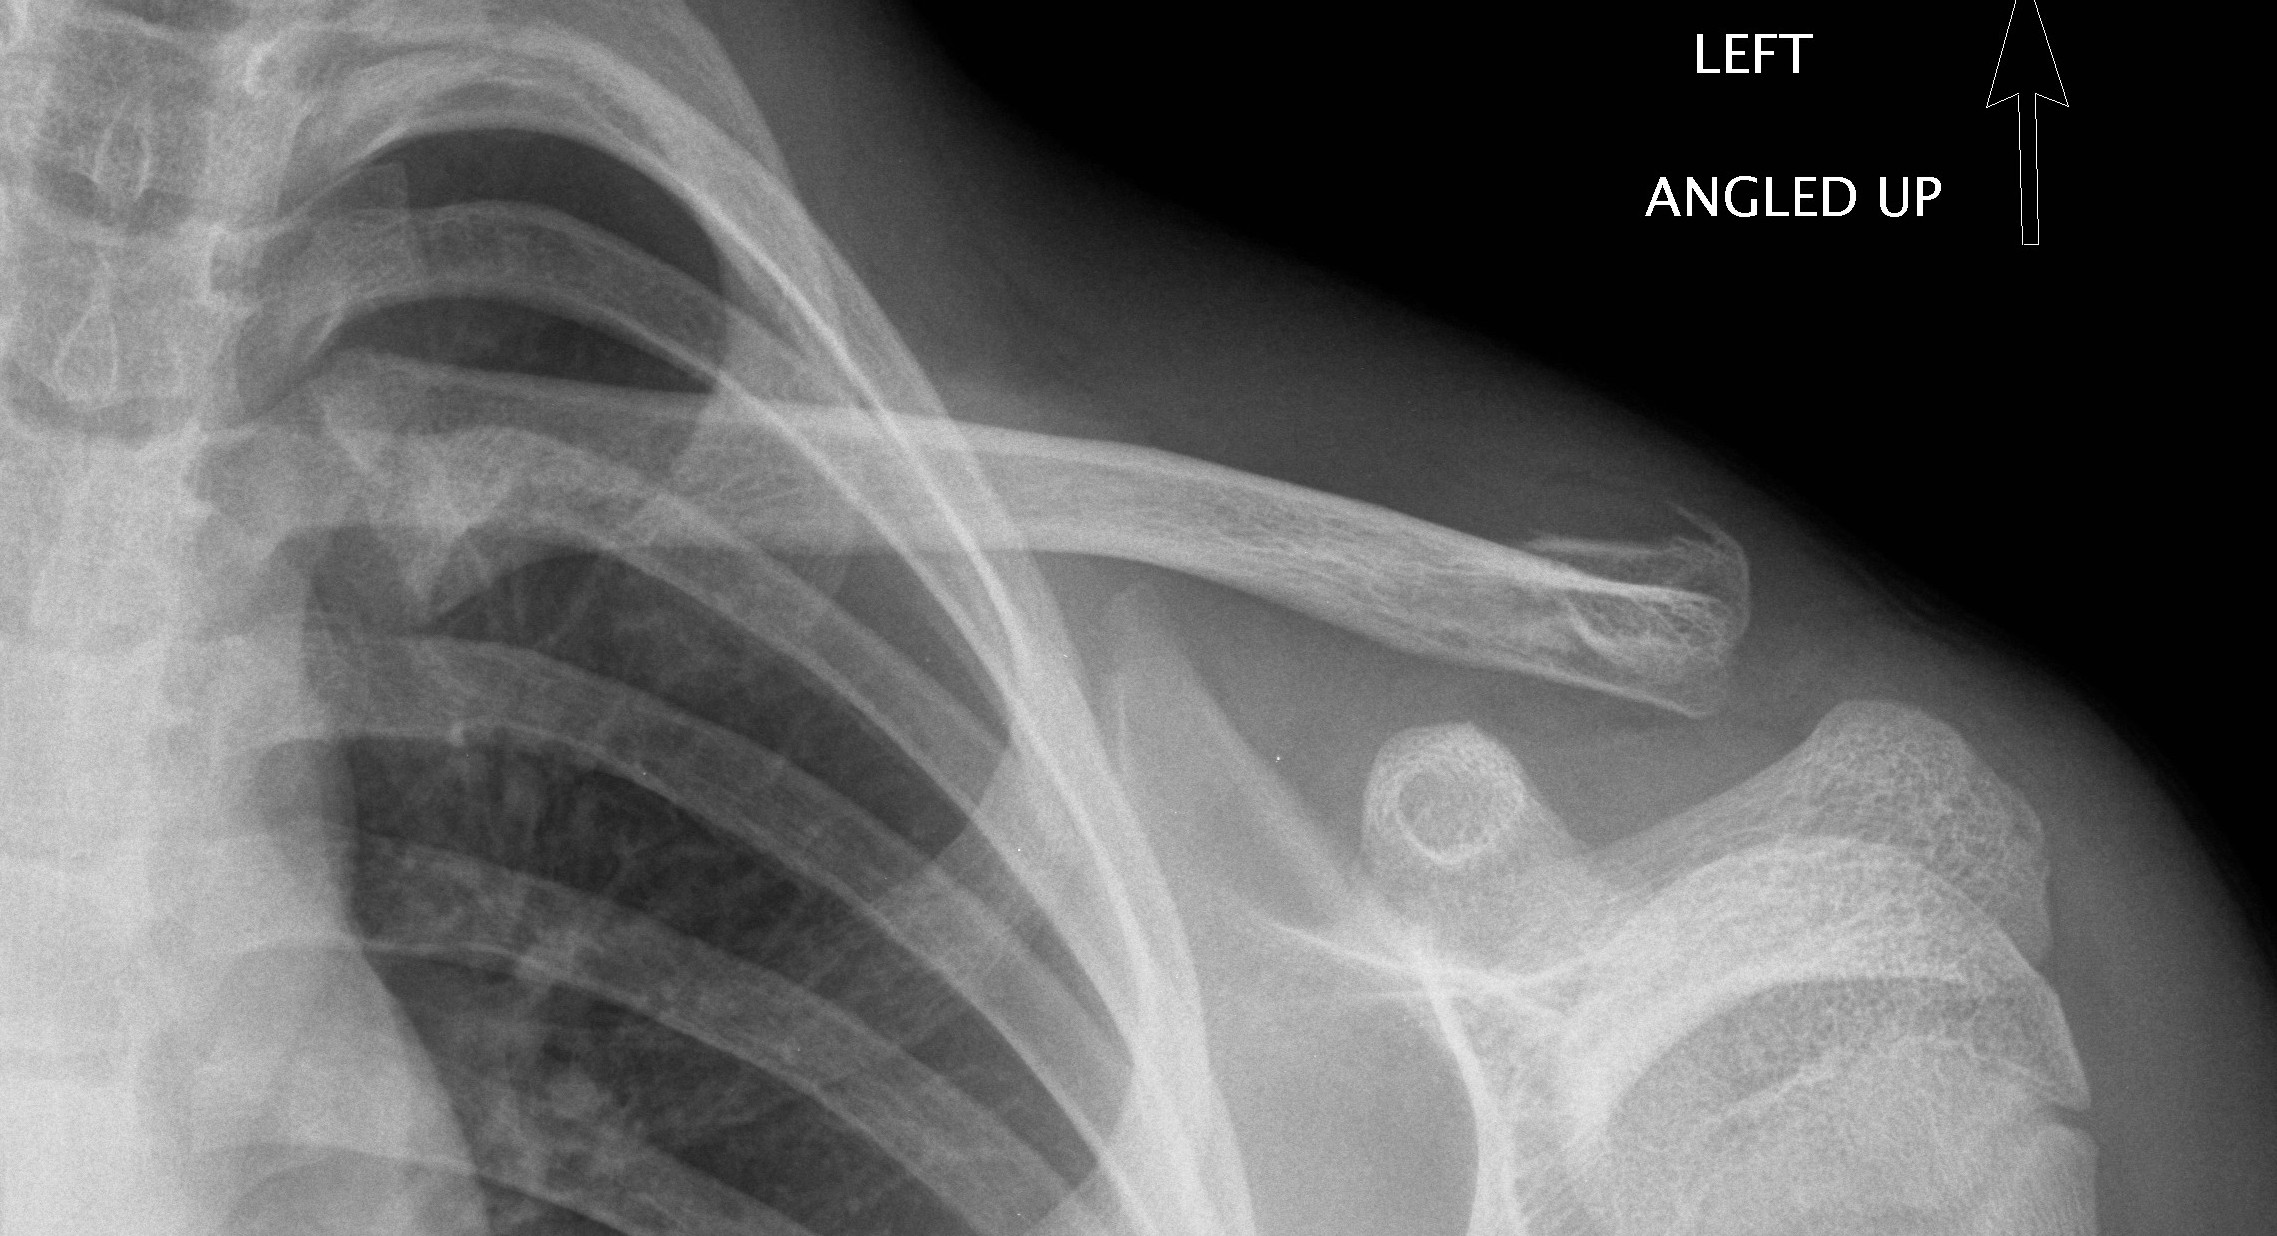

- Broad arm sling with referral to the Orthopaedic Fracture Clinic in 1-2 weeks’ time due to risk of non-union.

Displaced middle third clavicle fracture